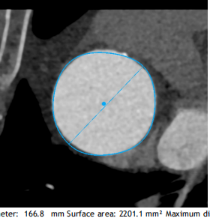

STJ周长:152.5mm,STJ高度:22.2mm;

升主动脉周长:166.6mm,最大直径54.5mm;